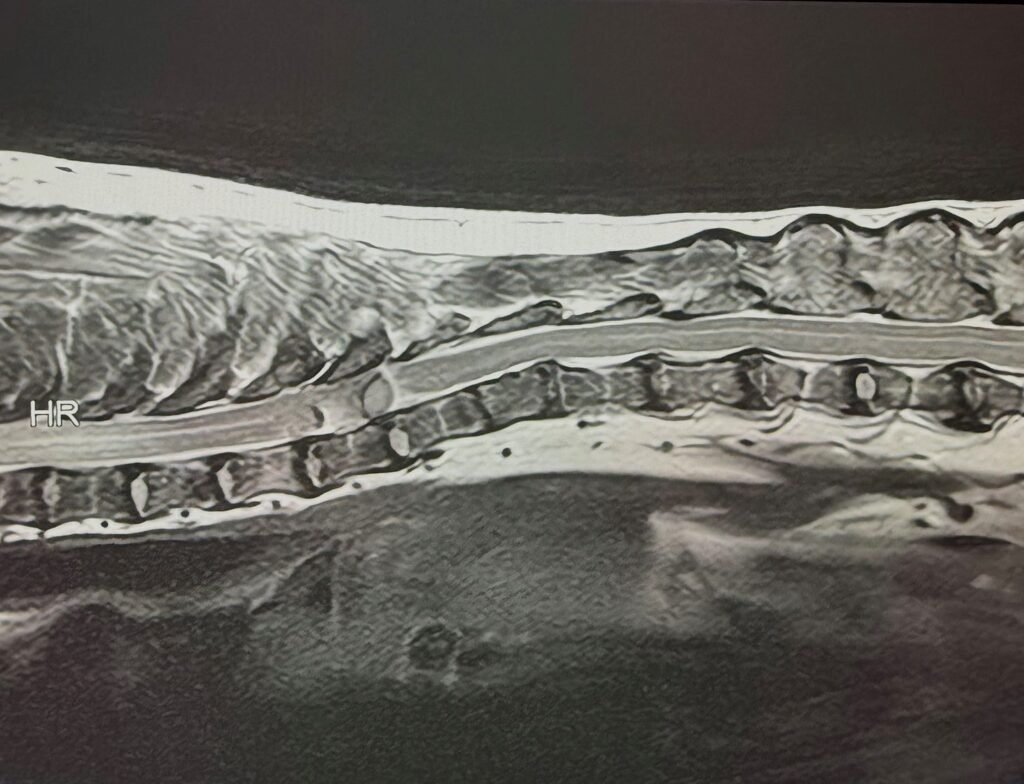

本症例は、数ヶ月前から後肢のふらつきがみられ、徐々に歩様の異常が進行したため紹介受診となりました。神経学的検査では後肢の姿勢反応低下が認められ、胸腰部脊髄病変が疑われました。MRI検査ではT8〜T10領域を中心に脊髄を圧迫する病変が確認され、硬膜外腫瘍が鑑別として挙げられました。臨床症状の進行と画像所見から、外科的減圧と病変の確定診断を目的に手術を選択しました。